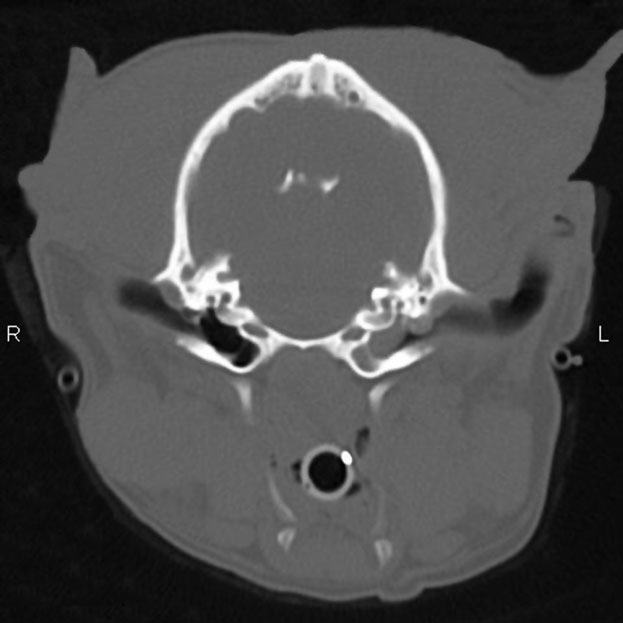

• computed tomography (CT)

Dr. Cole reported finding that tympanometry detected the PSOM in only

47% of ears with a flat pars flaccida.

She concluded that, in cavaliers

with a flat pars flaccida, only computed tomography (CT) scans can reliably detect PSOM in

the CKCS. CT scans require that the dog be under general anesthesia. The CT scan at the left, of a cavalier King Charles spaniel with

left-sided [L] unilateral PSOM, shows the soft tissue density completely

filling the bulla on the left side [L] and the airfilled bulla on the

right side. (From Dr. Cole's December 2015 report.)

She concluded that, in cavaliers

with a flat pars flaccida, only computed tomography (CT) scans can reliably detect PSOM in

the CKCS. CT scans require that the dog be under general anesthesia. The CT scan at the left, of a cavalier King Charles spaniel with

left-sided [L] unilateral PSOM, shows the soft tissue density completely

filling the bulla on the left side [L] and the airfilled bulla on the

right side. (From Dr. Cole's December 2015 report.)

In a December 2015 report, Dr. Cole examined 60 cavalier King Charles spaniels which had clinical signs suggesting PSOM. To diagnose the disorder, they used otoscopy, tympanometry, pneumotoscopy and tympanic bulla ultrasonography, in addition to using computed tomography (CT), which they stated was "the gold standard for the diagnosis of PSOM in the CKCS."